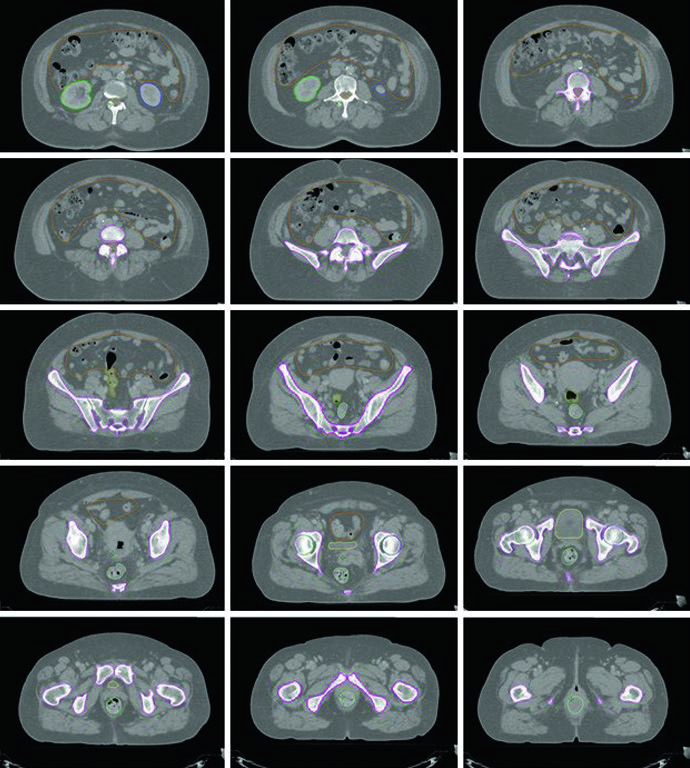

Um estudo com RM usando partículas de óxido de ferro injetadas demonstrou que 95% dos linfonodos pélvicos (ilíaco comum, ilíaco interno, ilíaco externo medial e anterior, e obturatórios) estão localizados dentro de 7 mm da vasculatura pélvica. Já os linfonodos inguinais devem ser delineados usando abordagem de compartimento anatômico, dada a maior variabilidade de localização em relação aos vasos.

Problemas frequentes observados em ensaios multicêntricos incluem: margem inadequada ao redor da vasculatura (CTV próximo demais dos vasos), cobertura insuficiente ao redor da vasculatura ilíaca interna inferior e posterior na pelve, cobertura insuficiente ao redor da vasculatura obturadora inferior e anterolateral, cobertura insuficiente da região pré-sacral e extensão desnecessária do CTV nas concavidades sacrais.

Se linfonodos para-aórticos estiverem envolvidos, deve-se empregar técnica de campo estendido, estendendo a borda cranial do CTV superiormente até o interespaço L1/L2 ou 3 cm cranial ao linfonodo mais superior envolvido. Os PTVs são criados para cada CTV e o PTV final é a combinação de todos. Expansões diferenciais CTV-PTV são utilizadas para cada componente baseadas no grau de movimento orgânico interno e incerteza de posicionamento.

O delineamento é similar à RT pélvica para câncer cervical. O GTV inclui toda doença macroscópica. O CTV se divide em CTV1 (GTV + útero inteiro), CTV2 (tecidos paravaginais/parametriais + 3 cm da vagina proximal) e CTV3 (igual ao cenário pós-operatório). Se a vagina distal (terço inferior) estiver envolvida, linfonodos inguinais devem ser contornados continuamente dos ilíacos externos até 2 cm caudal à junção safeno-femoral. Com envolvimento para-aórtico, campo estendido similar ao da Tabela 21.1. Expansões diferenciais: PTV1 = 15 mm, PTV2 = 7–10 mm, PTV3 = 5–7 mm. Boost adicional de 5–15 Gy pode ser adicionado para doença nodal macroscópica ou envolvimento parametrial, com SIB ou abordagem sequencial.